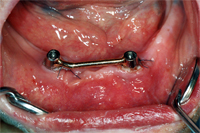

Dieser Fall zeigt eine seit Jahrzehnten gut bewährte Implantatsteglösung im zahnlosen Unterkiefer. Ohne diesen Steg würde die Prothese auf dem profilarmen Unterkiefer beim Sprechen und Essen instabil umherrutschen und das berüchtigte und unwürdige Prothesenklappern verursachen.

Bei diesem 79 Jahre alten, sehr aktiven Senioren haben wir zwei Implantate in der Eckzahnregion im Unterkiefer gesetzt. Zwei Monate später verbanden wir die Implantate starr mit einem Goldsteg (Abb. 11) und setzten die neue Prothese ein.

Die Abb. 12 zeigt die Unterkieferprothese mit Steghülse von innen. Im Mund eingesetzt hält die Prothese stabil und sicher (Abb. 13).